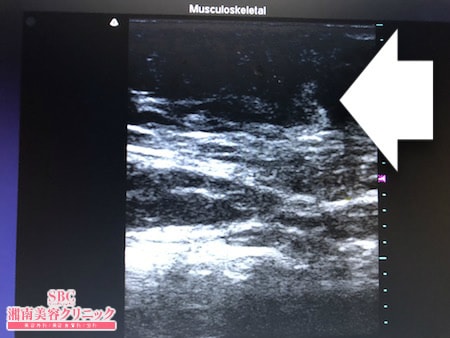

No.252299【脂肪吸引】外国でのおなかの脂肪吸引の再手術!もっと細くなりたいから取り残されたおなかの皮下脂肪を根こそぐ!上腹部術中タッチビュー

今回はその術中変化を見ていただきましょう。

前回の脂肪吸引で

ほどほどに皮下脂肪は吸引されていましたので

たくさんの皮下脂肪が残っていたわけではないのですが

今回は取り残された皮下脂肪を

徹底的に根こそました!